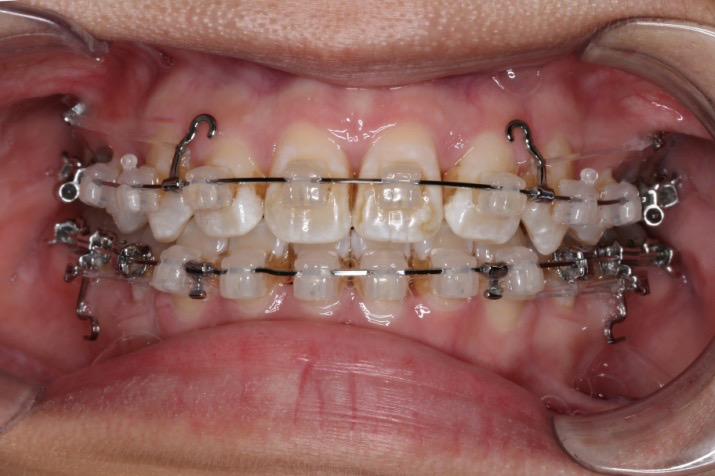

2016.10.31  初戴,0.013cu-niti2017.1.13  上颌加TPA,U56间斜形植入韩国庆北1312-08种植钉,上下0.16cu-niti

2017.02.16  上下0.014*25 cu-niti,50g 拉尖牙远中

2017.04.28

2017.04.28  上0.016*25ss 13、23近远中约5度 v形曲,下0.017*25ss

2017.05.26  磨牙近中倾斜,下颌36、46加power arm

2017.07.25

2017.07.25  上前牙加颈部弹力线

1.第0个月:2016.10.31 ◆ 初戴,0.013cu-niti

2.第2.5个月:2017.1.13 ◆ 上颌加TPA,植入1312-08种植钉,上下0.16cu-niti

3.第3.5个月:2017.02.16 ◆ 上下0.014*25 cu-niti,50g 尖牙远中

4.第6个月:2017.04.28 ◆ 上0.016*25ss 13/23v形曲,下0.017*25ss

5.第7个月:2017.05.26 ◆ 下颌36/46加power arm

6.第9个月:2017.07.25 ◆ 上前牙加颈部弹力线

7.第13.5个月:2017.12.15 ◆ 36/46远中倾斜,改变下颌牵引位置